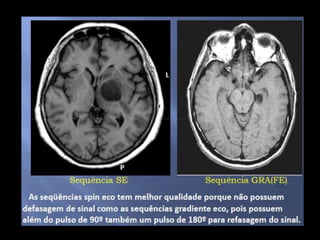

DIFERENÇAS ENTRE GRE E SE

• Não utilizapulsos de 180°, mas utiliza as bobinas gradientes para refasar os spins. • Defasagem do sinal-D.I.L • Pouca resolução espacial • Sensibilidade a artefatos magnéticos DIFERENÇAS ENTRE GRE E SE